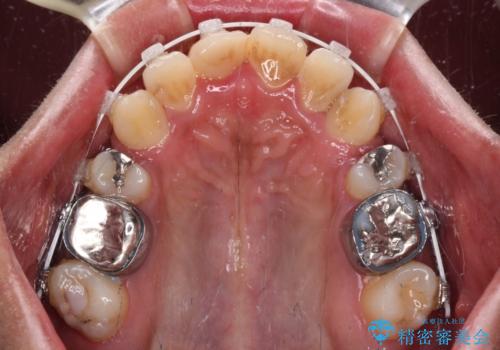

八重歯と開咬 ワイヤー装置での抜歯矯正

- 審美装置

- 前歯のデコボコと八重歯、開咬を気にして来院された患者様です。

骨格的に下顎骨が上顎骨に対して後退位であったため、上顎の左右第一小臼歯を抜歯し、デコボコを改善するとともに開咬を改善していくこととしました。

自己管理が煩わしいとのことで、表側のワイヤー装置にて治療を進めて行くこととしました。

舌の突出癖により開咬となっていたため、突出癖改善のためのトレーニングをしっかりと行っていただき、予定の期間で無事に治療を終えることができました。